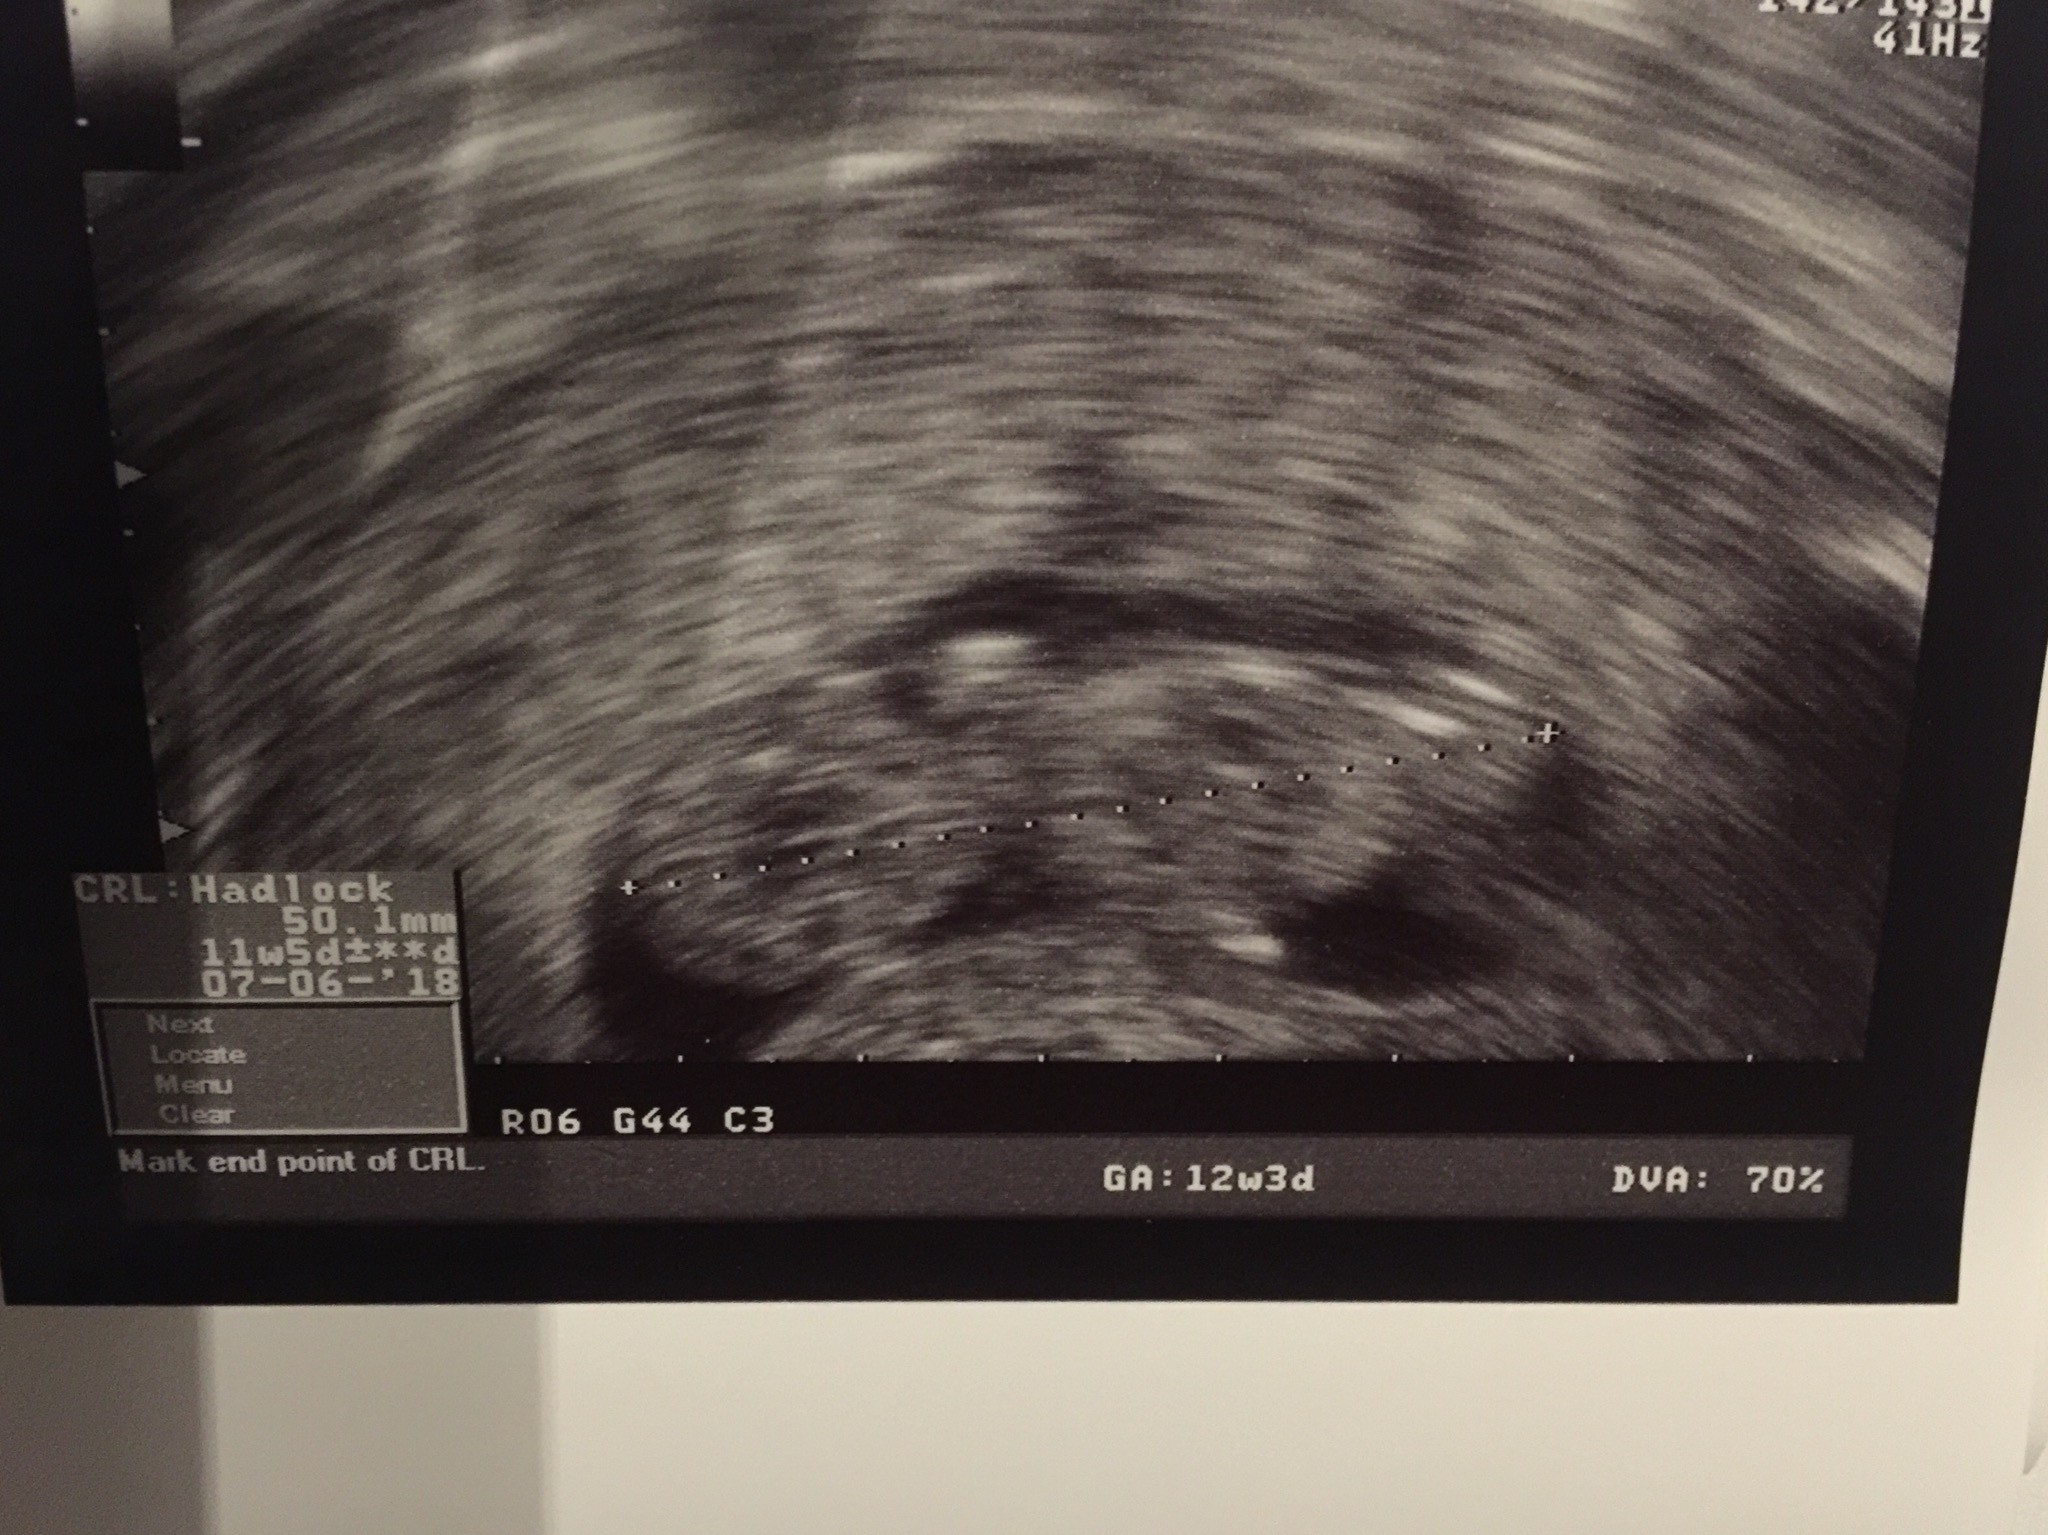

Witam w 19 tygodniu ciąży dowiedziałam się ze będę miała dziewczynkę w 20 tyg okazało się jednak , że to chłopak. Sama już nie wiem bo na jednym usg widać na pewno dziewuche a na drugim chłopca. Może to pempowina ?? Może ktoś mi pomoże rozwiązać ta zagadkę

Załączniki

• 4A8F5FF1-76CA-4DE0-AC12-5EDF08E820F2.jpg

4A8F5FF1-76CA-4DE0-AC12-5EDF08E820F2.jpg

596,4 KB · Wyświetleń: 44 148